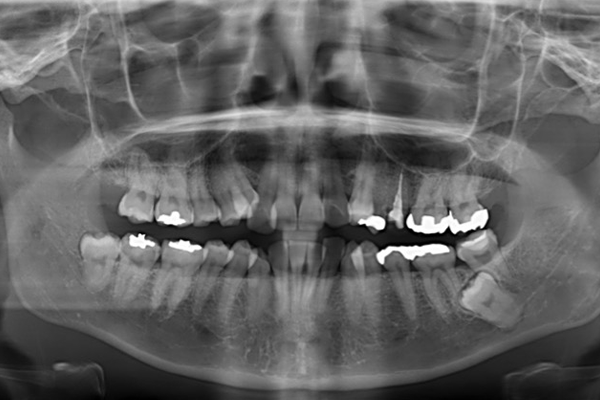

2.レントゲン検査

(パノラマ・セファロ)

矯正診断で特に重要なのがレントゲン検査です。

⚫︎パノラマX線

歯の本数や位置、虫歯や歯周病の有無、親知らずの状態を確認します。

⚫︎セファロX線(頭部X線規格写真)

顎の骨格の大きさやズレ、上下顎の位置関係、成長方向を分析するために必須の検査です。

これらのデータは、矯正治療の「設計図」となる重要な役割を果たします。